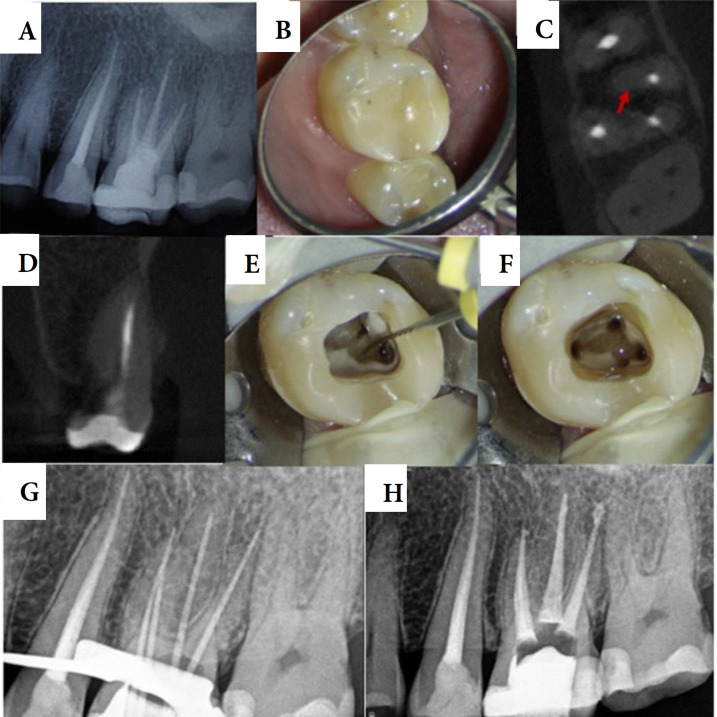

The patients with unusual symptoms present a diagnostic challenge for clinicians and may lead to misdiagnoses and inappropriate or unnecessary treatments. Endodontic diseases can present with a variety of symptoms, and it is possible for odontogenic pain to resemble non-odontogenic pain, which can complicate treatment due to the distinct management plans of the two conditions. This report details the successful management of vague pain, and popping sensations in the left maxilla triggered by cold exposure. Previous clinicians were unable to identify the pain's origin, leading to unnecessary treatments. A clinical examination, and cone-bean computed tomography evaluation revealed the presence of a missed second mesiobuccal root canal. The canal was located using an operating microscope and ultrasonics. Non-surgical endodontic retreatment was completed in two visits, successfully. This report highlights the critical importance of identifying the diverse symptoms that may arise from endodontic origin, as these can complicate clinical diagnosis.